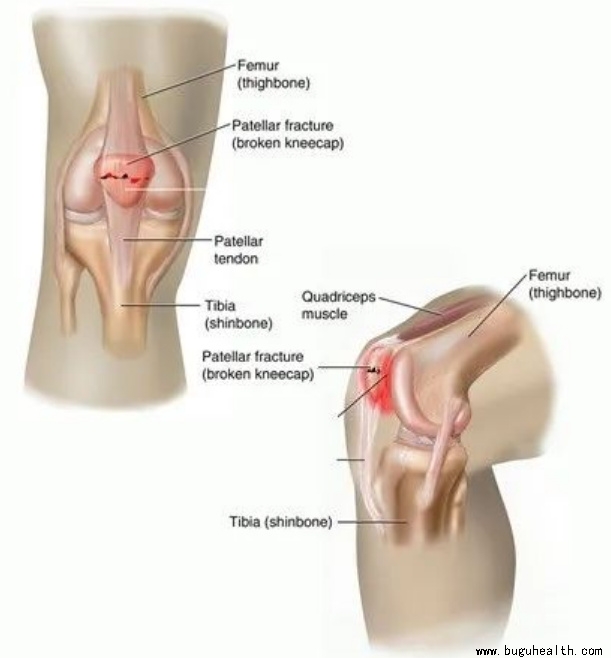

4. 髌骨骨折

属于膝盖骨折,髌骨是膝关节的重要组成部分,髌骨骨折后常发生膝关节肿胀积血,髌前可见皮肤擦伤及皮下血肿,压痛明显,有移位的骨折可触及骨折间隙。

未移位骨折或移位不太明显可保守治疗

保守治疗主要是指:

①固定,石膏或支具固定根据医生的建议时间复诊,如果最终稳定,可佩戴石膏或支具直到伤后4~6周拆除石膏,直到骨痂更可靠。

②积极康复训练,包括膝盖的主动及被动活动,以及渐进式恢复运动强度,避免髌骨顽固粘连。

何时可以进行康复训练?

保守治疗:

髌骨骨折移位不明显,关节面比较平整,绝大部分采用石膏或支具固定来维持位置,这种情况一般需要固定四周左右,然后进行适当的康复训练。

手术治疗:

较为简单的骨折,术后1-2周就可以进行膝关节适度屈伸活动锻炼;

如果骨折非常严重,比如粉碎性骨折等需要根据手术固定方式选择康复治疗方法,可能需要2-4周的休息和关节活动的限制,期间需要在康复医生的指导下进行维持临近关节活动度和肌力的训练。